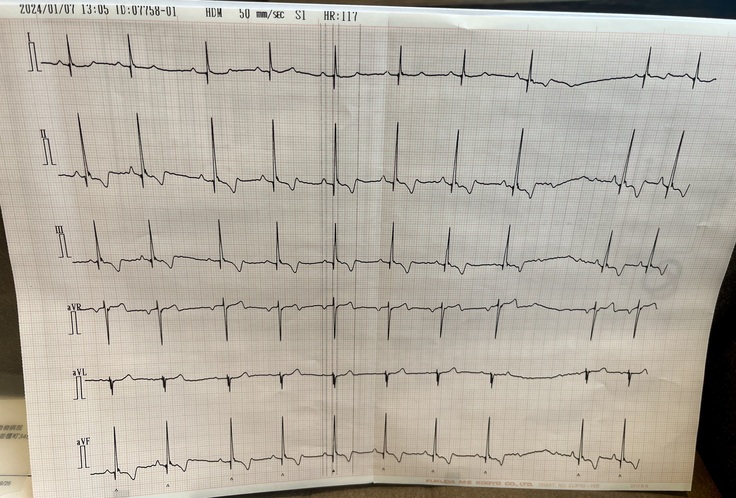

心臓の状態は経過が良く

レントゲン、エコー、血圧の検査結果から

問題無く順調に回復しておりました✨

心臓もかなり小さくなり

僧帽弁、三尖弁共に軽度の逆流は残るものの